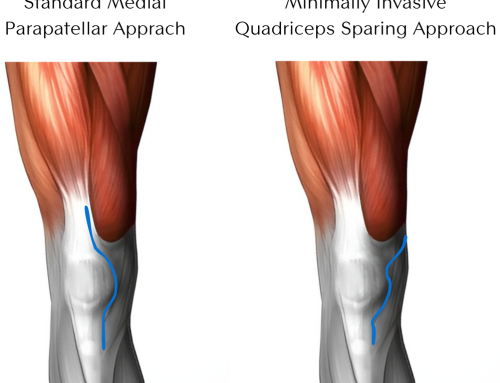

There are a few differences in the beginning stages of recovery depending on the approach. Depending on your body shape, size, and status of your hip, your surgeon may approach the hip from posterior (the back side) or anterior (the front side).

The posterior approach requires six weeks of restrictions on how much you can flex your hip, rotate it in, and cross it over midline. In the anterior approach, your limitations are less severe. Patients usually need to be mindful of passive stretching of the front of their hip joint, but it is much less common to require restrictions. The specific details should be discussed with your surgeon and Physical Therapist. Your Physical Therapist will also work with you throughout your recovery, providing guidance and encouragement, and helping you reach your goals.

Range of motion and flexibility are also essential. But this may be slower to address than strengthening or balance as you may have restrictions on how your leg can be moved, based on the approach taken to replace your hip.

Your Physical Therapist will be the one to initiate mobility exercises as they can passively move your hip around, stopping before they go too far. Then over time, as this passive movement improves without pain and as you are outside of your six-week restrictions, you may start to move and stretch your hip further, using pain as your guide.